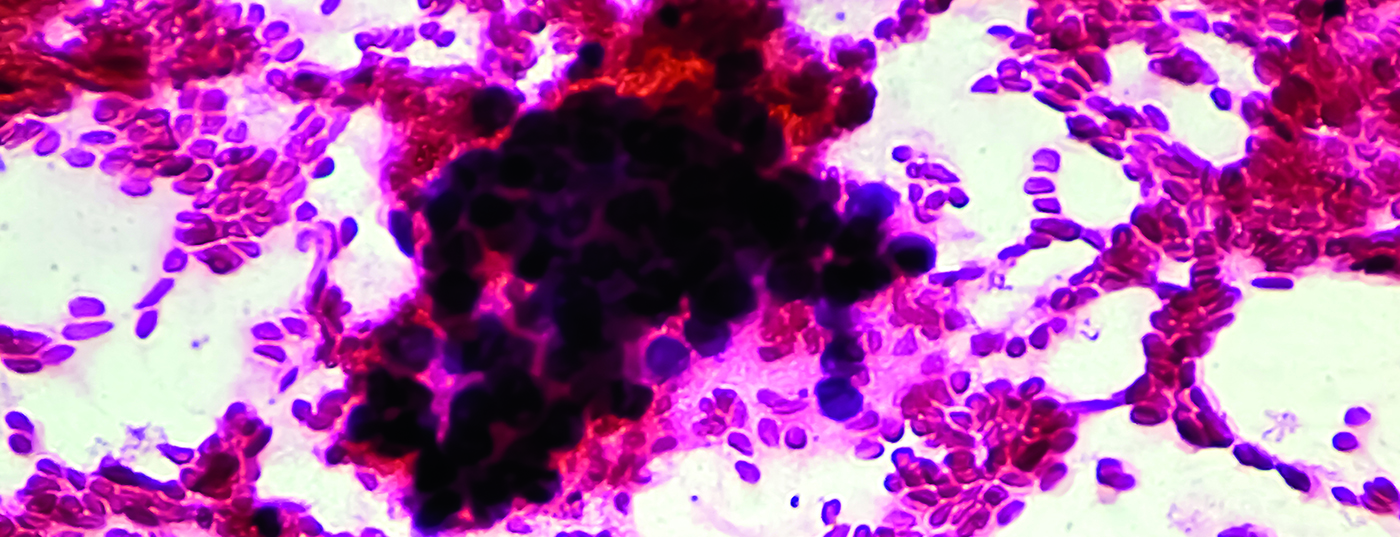

Leberkrebs ist die dritthäufigste krebsbedingte Todesursache weltweit. Bislang sind die Behandlungsmöglichkeiten von zwei Leberkrebsarten, das hepatozelluläre Karzinom (HCC) und das Cholangiokarzinom (CCA), unzureichend, bei zugleich steigender Tendenz an Neuerkrankungen. Hoffnung macht nun eine Studie von Forschenden der Medizinischen Hochschule Hannover (MHH) und des Helmholtz-Zentrums für Infektionsforschung (HZI). Ein Impfstoff auf Basis eines stark abgeschwächten Infektionserregers namens Listeria monocytogenes erwies sich in präklinischen Mausmodellen als sicherer und wirksamer Schutz bei prämalignen und malignen Lebererkrankungen.